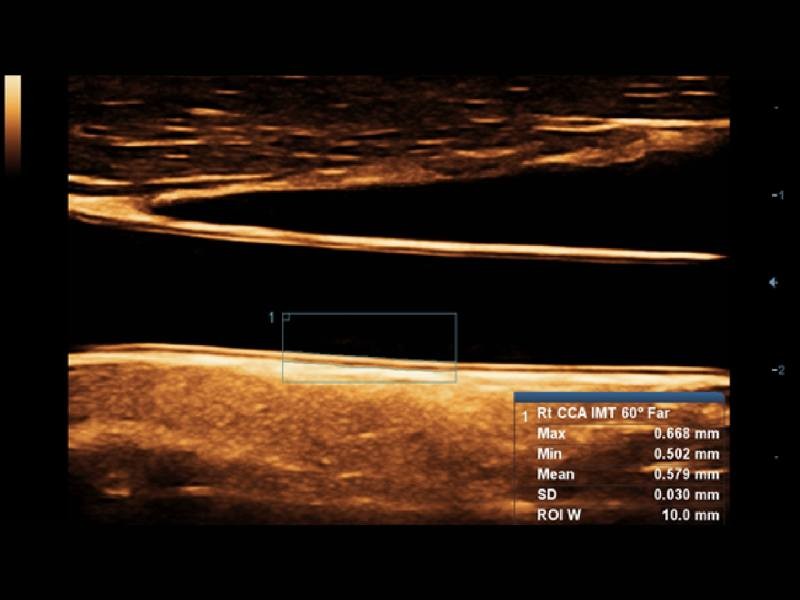

Comparados aos transdutores tradicionais, os transdutores ComboWave utilizam um novo tipo de material piezoelétrico composto a fim de otimizar drasticamente o espectro acústico e reduzir a impedância acústica. Melhor integrados à exclusiva tecnologia 3T da Mindray, os transdutores lineares ComboWave permitem desfrutar de um desempenho excepcional proporcionado por incríveis resoluções e consistência das imagens em tireoide, mama, vascular e mais.